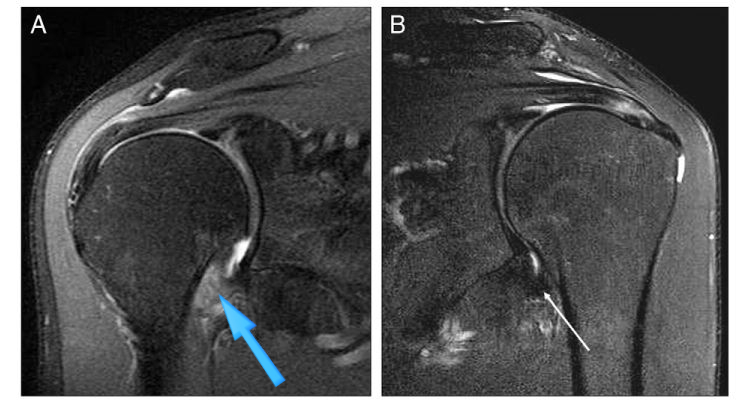

(좌) 병변측 (우) 정상측

좌측이 아픈 어깨입니다.

화살표에 표시된대로

우측에 비해 밝고 두꺼워져 있죠?

이번엔 우측이 문제인데요.

염증으로 두꺼워지고 위축되어

관절용적이 감소했습니다.